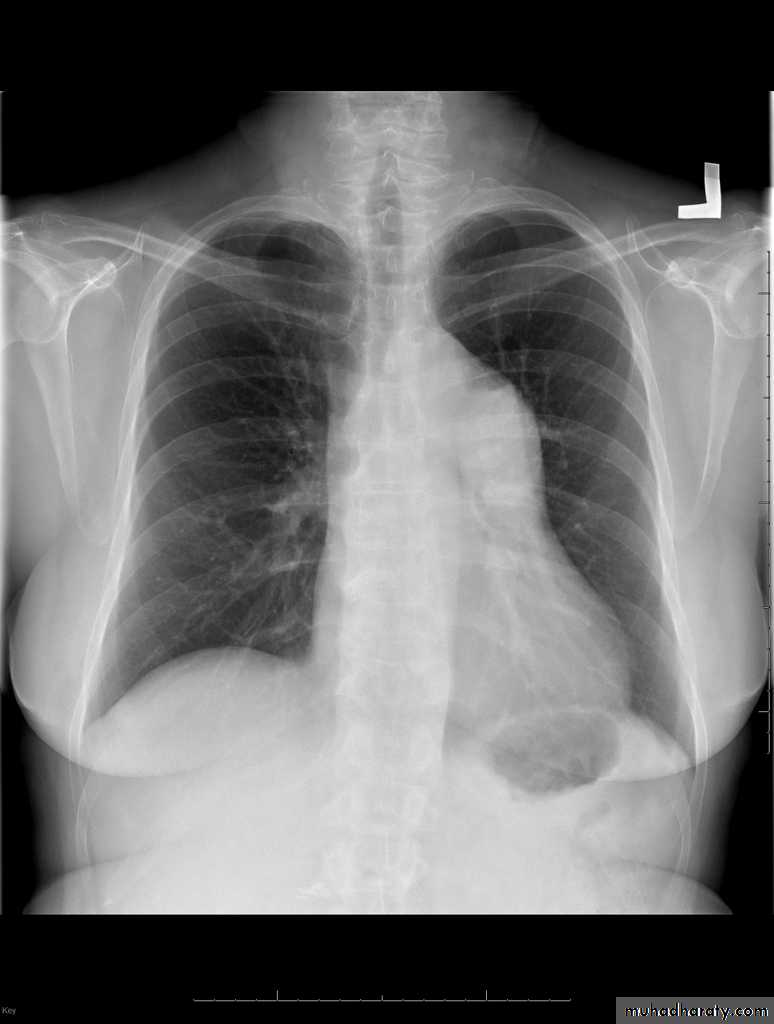

CXR:

Oligemic lungs: reduced pulmonary blood flow

Prominent main pulmonary artery (post-stenotic dilatation)

Coarctation of the Aorta: Investigations

CXR:Rib notching: from enlarged collaterals

Prestenotic and post-stenotic dilatation form the “3 sign” of the descending aorta